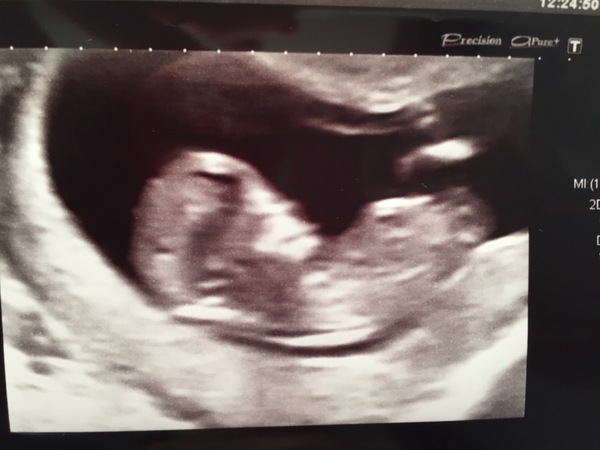

I'm delighted to guess! Just wanted to add my disclaimer. This is how they showed me my scan's professed nub. I'm pretty sure it could be anything GrinConfused

December 2017 babies #6 - dating scans, gender reveals, the beginning of bumps & the 2nd trimester!

I think you are right - looks like the stacking they talk about. Look at me the expert now Grin